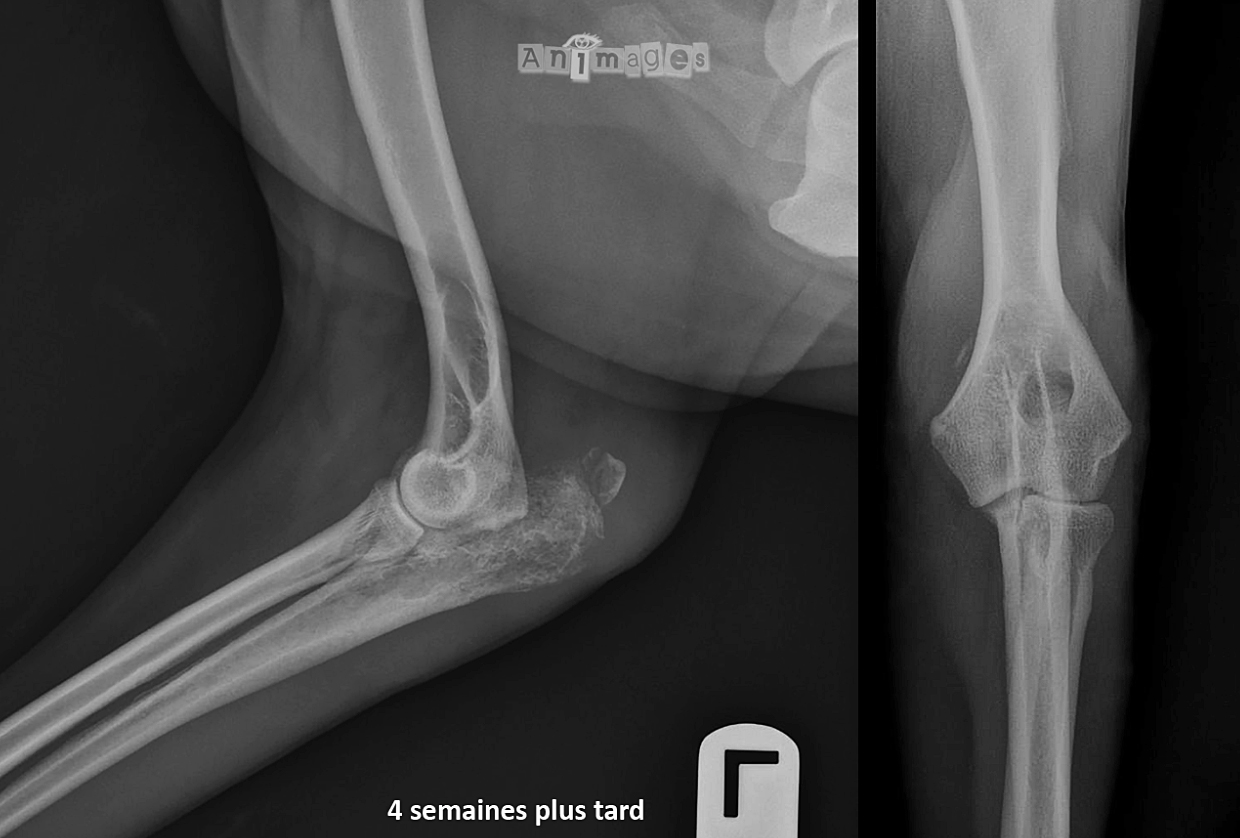

Pas grand chose n’est-ce pas ? Comme la boiterie de Fugasse progressait sans répondre aux anti-inflammatoires, de nouvelles radiographies ont été prises 4 semaines plus tard…